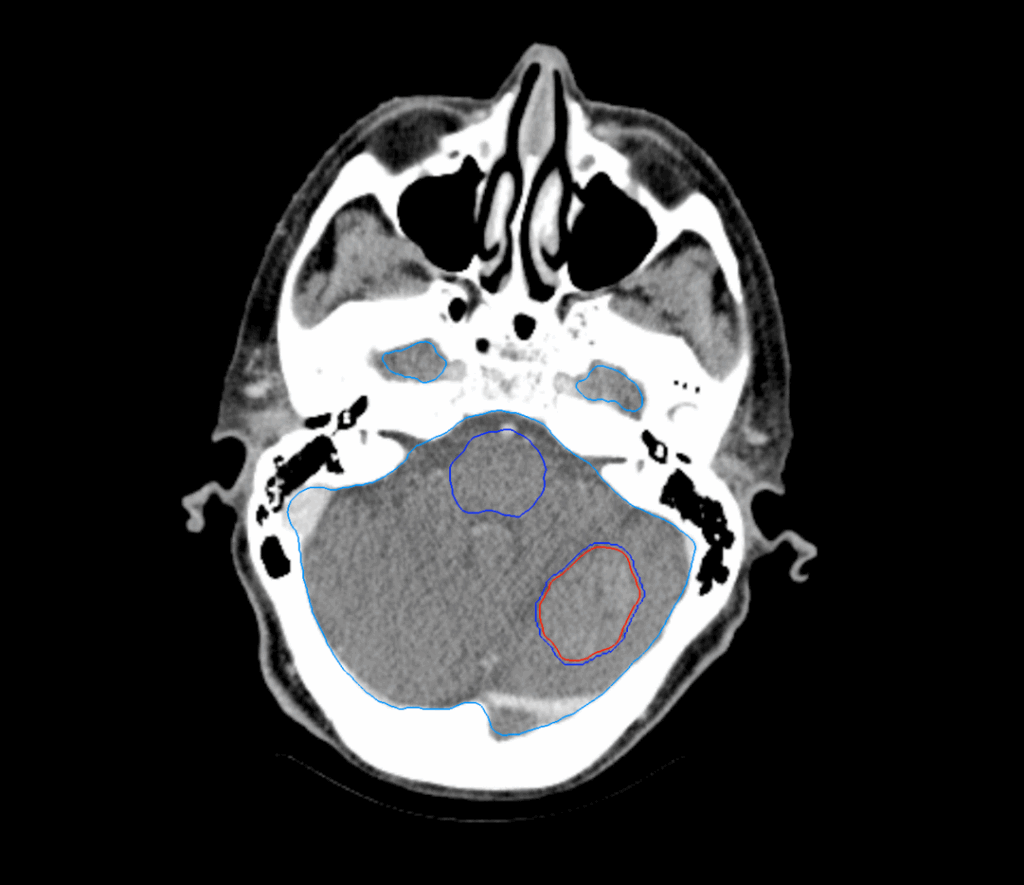

8 Brain Metastases

< View All Plan Studies CYBERKNIFE SYSTEM 8 Brain Metastases Case History AGE: 56-year-oldGENDER: Male Medical History Small Cell Lung Cancer (SCLC), diagnosed and treated eight months ago: Chemotherapy and radiotherapy for the primary lung tumor. No prophylactic cranial irradiation was administered Follow-up MRI: 8 metastases in the brain Planning CT Images Treatment Plan Images […]

One Brain Metastasis

< View All Plan Studies CYBERKNIFE SYSTEM One Brain Metastasis Case History AGE: 65-year-oldGENDER: Female Medical History Small Cell Lung Cancer (SCLC), diagnosed and treated six months ago: Surgical resection of the primary lung tumor followed by adjuvant chemotherapy and radiotherapy Patient has been experiencing headaches, dizziness, and occasional balance issues MRI: metastasis in the cerebellum, […]